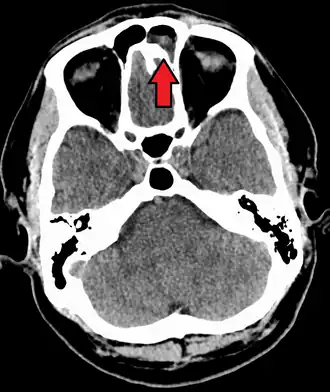

-

CT of chronic sinusitis -

CT scan of chronic sinusitis, showing a filled right maxillary sinus with sclerotic thickened bone -